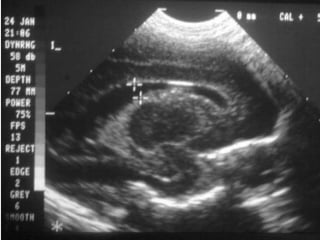

•20- 23.6 SDGINMADURO

•26-32 SDGPRETERMINO

EXTREMO

•32-36 SDGPREMATURO

•37-42 SDGTERMINO

•MAS DE 42 SDGPOSTERMINO